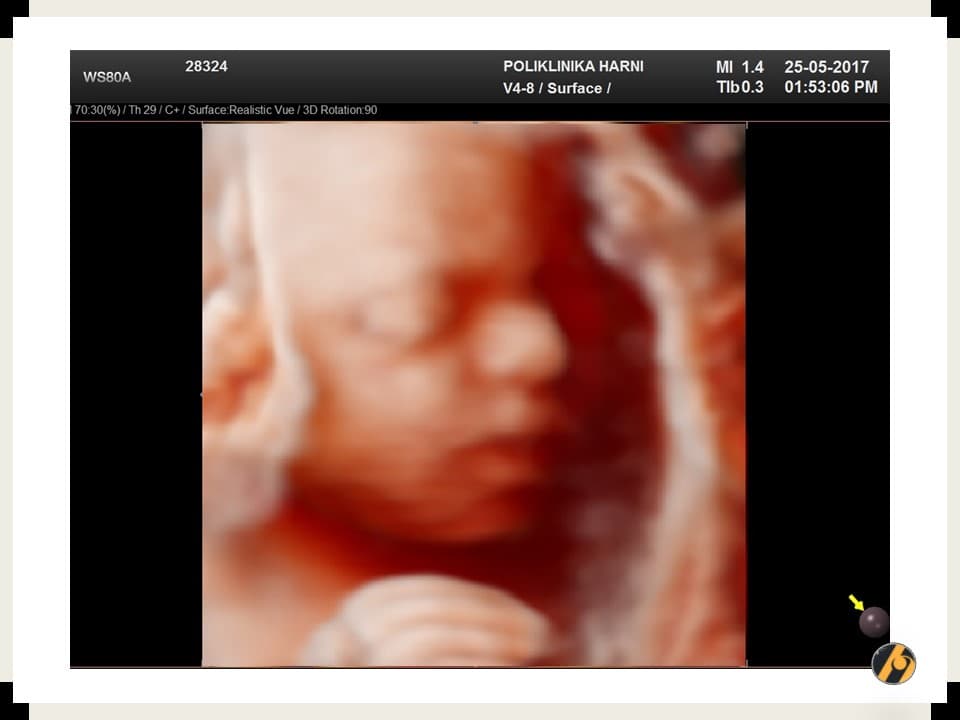

Fetus je dug približno 24 do 25 cm i težak oko 280 do 300 g. Pokreti postaju snažniji, razvijaju se osjetila, a kožu štiti sloj verniksa.

Duljina bebe od vrha glave do pete iznosi oko 25 cm, a težina je približno 300 grama. Tijelo postaje sve proporcionalnije, iako je glava još uvijek relativno veća u odnosu na ostatak tijela.